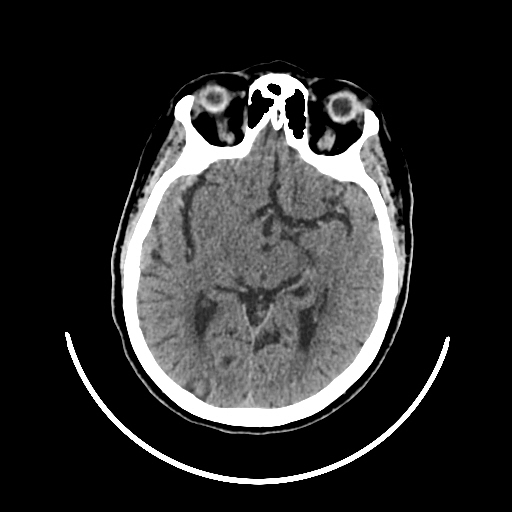

A 75 years old woman with DM-2 since 3 years

Patient O/E images:

C/O: Breathlessness X 2-3 day's

Vomiting 1-2 episode since last night

Cough X 2-3 day's

H/O: unconsiouness since few hour's at home around 10:30 pm

K/C: DM / HTN since 2-3 year's